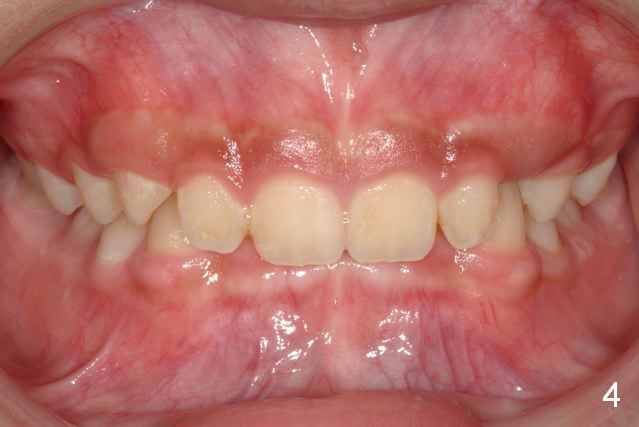

A 11-year-old boy has shorter lower 1/3 face (Fig.1,2) with light concave profile, especially the lower lip (Fig.3).  There is anterior deep bite (Fig.4) with Class II posterior occlusion (Fig.5,6).  UL2 is microdontia (Fig.7 *), while the Lower Es are retained (Fig.8).  Preop (2015_01_07) Ceph (Fig.9) and Pan (Fig.10) show ectopic L7s and congenitally missing L5s.

Brackets were placed on 2015_09_06 (Fig.11-13, Phase I pre-orthopedic tooth movement, leveling in advance of Herbst appliance therapy using ankylosed Es).   Six months later (Fig.14-16), LR7 did better, LL7 did not and will need intervention. But intrusion of L 3-3 looks good.